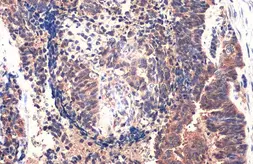

Images

Applications